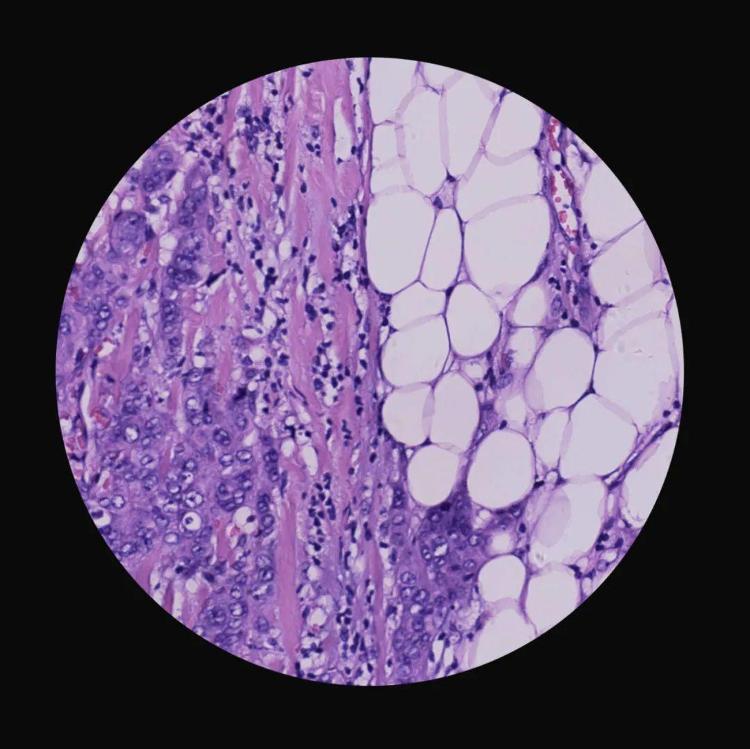

《生死较量》(组照) 李元鹏 摄影